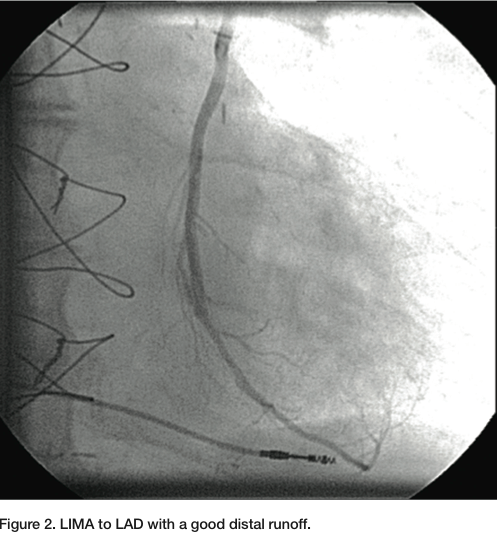

A 6 French (Fr) Glidesheath (Terumo) was inserted in the left radial artery. A Judkins right (JR) 4 catheter was advanced from the left radial over a J wire. The left subclavian angiogram showed a 100% chronic total occlusion (CTO) of the left SA proximal to LIMA origin (Figure 1). There was biphasic flow in the left vertebral artery, suggesting the left subclavian artery was filled by collaterals through the cerebral circulation. The LIMA was free of any disease and there was good LAD runoff (Figure 2). The right femoral artery was accessed with a 6 Fr